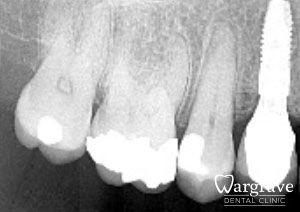

Healthy Smiles These are more advanced examples of different treatments available.All cases shown were carried out by Dr R Khurana unless otherwise stated. Immediate implants Anterior Mandible Bone Regeneration Anterior Mandibular Implant Bridge Maxillary Anterior Implant Bridge Implant stabilised ‘Life Like’ replacement dentures Implant Bridge after 10-years with zero bone loss Implant examples including ZBLC concepts Adhesive Bridge solution for a missing premolar Multidisciplinary care Orthodontics, Replacement veneers and composite bonding Adhesive Bridge solution for missing central incisors Replacement crown, Veneer and Composite Bonding Replacement Crowns and Veneer Injection Moulding using Composite Resin Equilibration Tooth Whitening to treat Developmental Discolouration